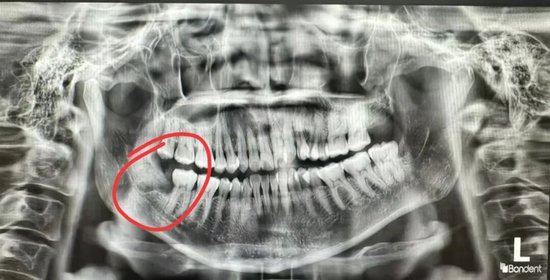

张女士的困扰由来已久,右下智齿不仅让她吃不下饭、夜不能寐,更让她痛苦的是一平躺就天旋地转,日常睡觉需垫三个枕头。然而智齿情况不容乐观,拍片显示智齿横向生长,牙根粗壮且紧贴下牙槽神经,一旦损伤神经,可能导致下巴、下唇终身麻木;加上张女士张口幅度仅能容纳两根半手指,常规平躺拔牙的操作方式在她身上完全行不通。

为确保手术万无一失,医护团队术前做足准备,将吸引器、挺子、涡轮手机等器械按操作顺序摆放成“流水线”,明确左右手分工,最大限度节省手术时间。手术中,徐主任弯腰悬臂,精准操作,先用微创刀片划开牙龈暴露牙冠,再用高速手机将横向牙冠磨成两瓣减小体积,随后一点点去骨“剥离”粗壮牙根;遇到靠近神经的部位,便换用小一号车针轻提慢磨,宁可多花费时间也绝不冒险。